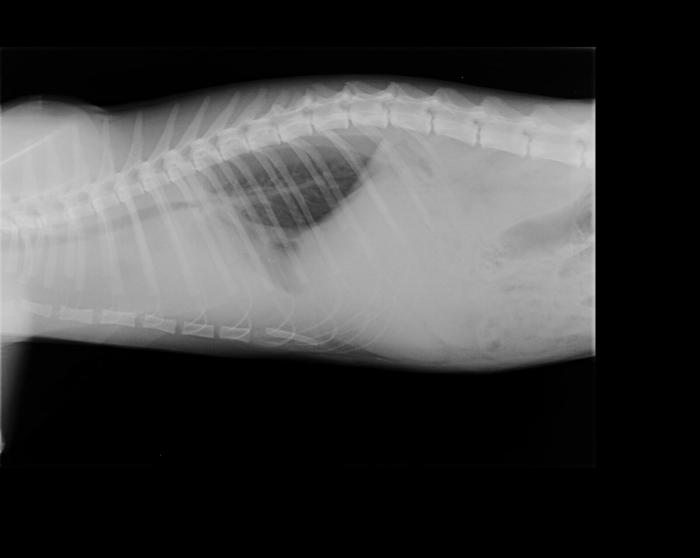

Debe llevarse a cabo con un animal estabilizado y con respiración normal (es decir, jamás con un paciente disneico o cuya oximetría de valores por debajo de lo normal). Es el método más práctico para evaluar tanto continente como contenido de la cavidad torácica, siendo conveniente solicitar al menos dos incidencias (por lo general se realiza laterolateral izquierdo o derecho y dorsoventral o ventrodorsal según el paciente lo permita). Así, se evalúa no solo si existe alguna alteración puntual de la cavidad sino también qué hemitórax se encuentra más afectado, si lo hubiera. Este método permite observar, aparte de la existencia de colectas, fracturas de costilla, rupturas diafragmáticas, presencia de masas, desviaciones viscerales, cuerpos extraños, agrandamiento de la silueta cardíaca o alteración de los patrones vasculares. Los signos radiológicos de colecta de aire son los siguientes: retracción de uno o ambos pulmones con respecto de la pared torácica, mayor densidad del pulmón debido a su colapso, desplazamiento dorsal de la silueta cardíaca.

En el caso de colectas líquidas se hallan: fisuras interlobares ensanchadas, con aumento de densidad de tejidos blandos, retracción del pulmón, quedando un espacio entre este y la pared con radiodensidad similar a los tejidos blandos, redondeamiento de la fisura costofrénica, disminución de visibilidad de la silueta cardíaca y contorno diafragmático poco definido (Figura 3A-B).